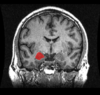

Function of precentral gyrus

Motor cortex.

Contralateral movement of face, arm, leg, trunk

Lesion to this area would result in?

This is the precentral gyrus

Monoplegia or hemiplegia depending on extent of damage